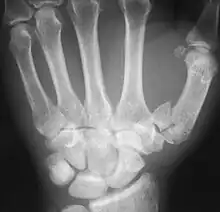

First metacarpal bone

The first metacarpal (Left)

The first metacarpal bone or the metacarpal bone of the thumb is the first bone proximal to the thumb. It is connected to the trapezium of the carpus at the first carpometacarpal joint and to the proximal thumb phalanx at the first metacarpophalangeal joint.

The first metacarpal bone is short and thick with a shaft thicker and broader than those of the other metacarpal bones. Its narrow shaft connects its widened base and rounded head; the former consisting of a thick cortical bone surrounding the open medullary canal; the latter two consisting of cancellous bone surrounded by a thin cortical shell. [1]

The head is less rounded and less spherical than those of the other metacarpals, making it better suited for a hinge-like articulation.

The distal articular surface is quadrilateral, wide, and flat; thicker and broader transversely and extends much further palmarly than dorsally. On the palmar aspect of the articular surface there is a pair of eminences or tubercles which articulate with the radial and ulnar sesamoid bones of the thumb metacarpophalangeal joint; the lateral eminence is larger than the medial.